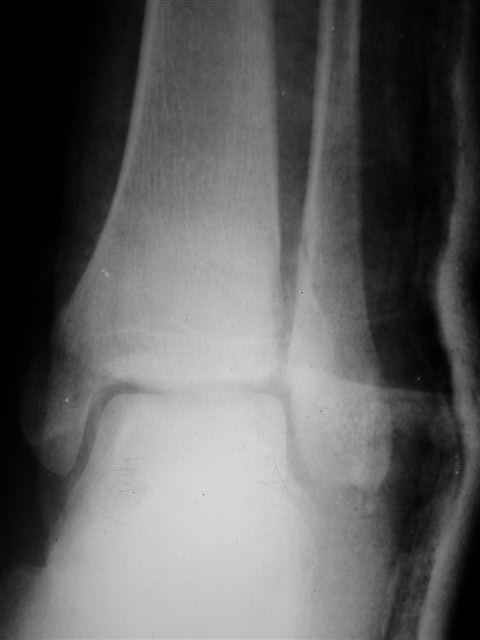

> интересуюсь тактикой лечения повреждений голеностопного сустава.

Ничего сверхъестественного, но если есть интерес, то в понедельник пересниму Рг-граммы и отправлю.

Я предупреждал, что ничего сверхъестественного. Каюсь, что одна из спиц прошла несколько дальше, чем нужно было, но главное - перелом стабилизирован и больной работает суставом в полном объёме, несмотря на представленную раннее травму коленного сустава.